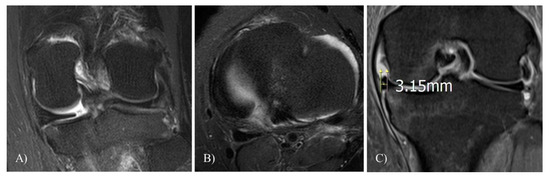

Meniscal Extrusion